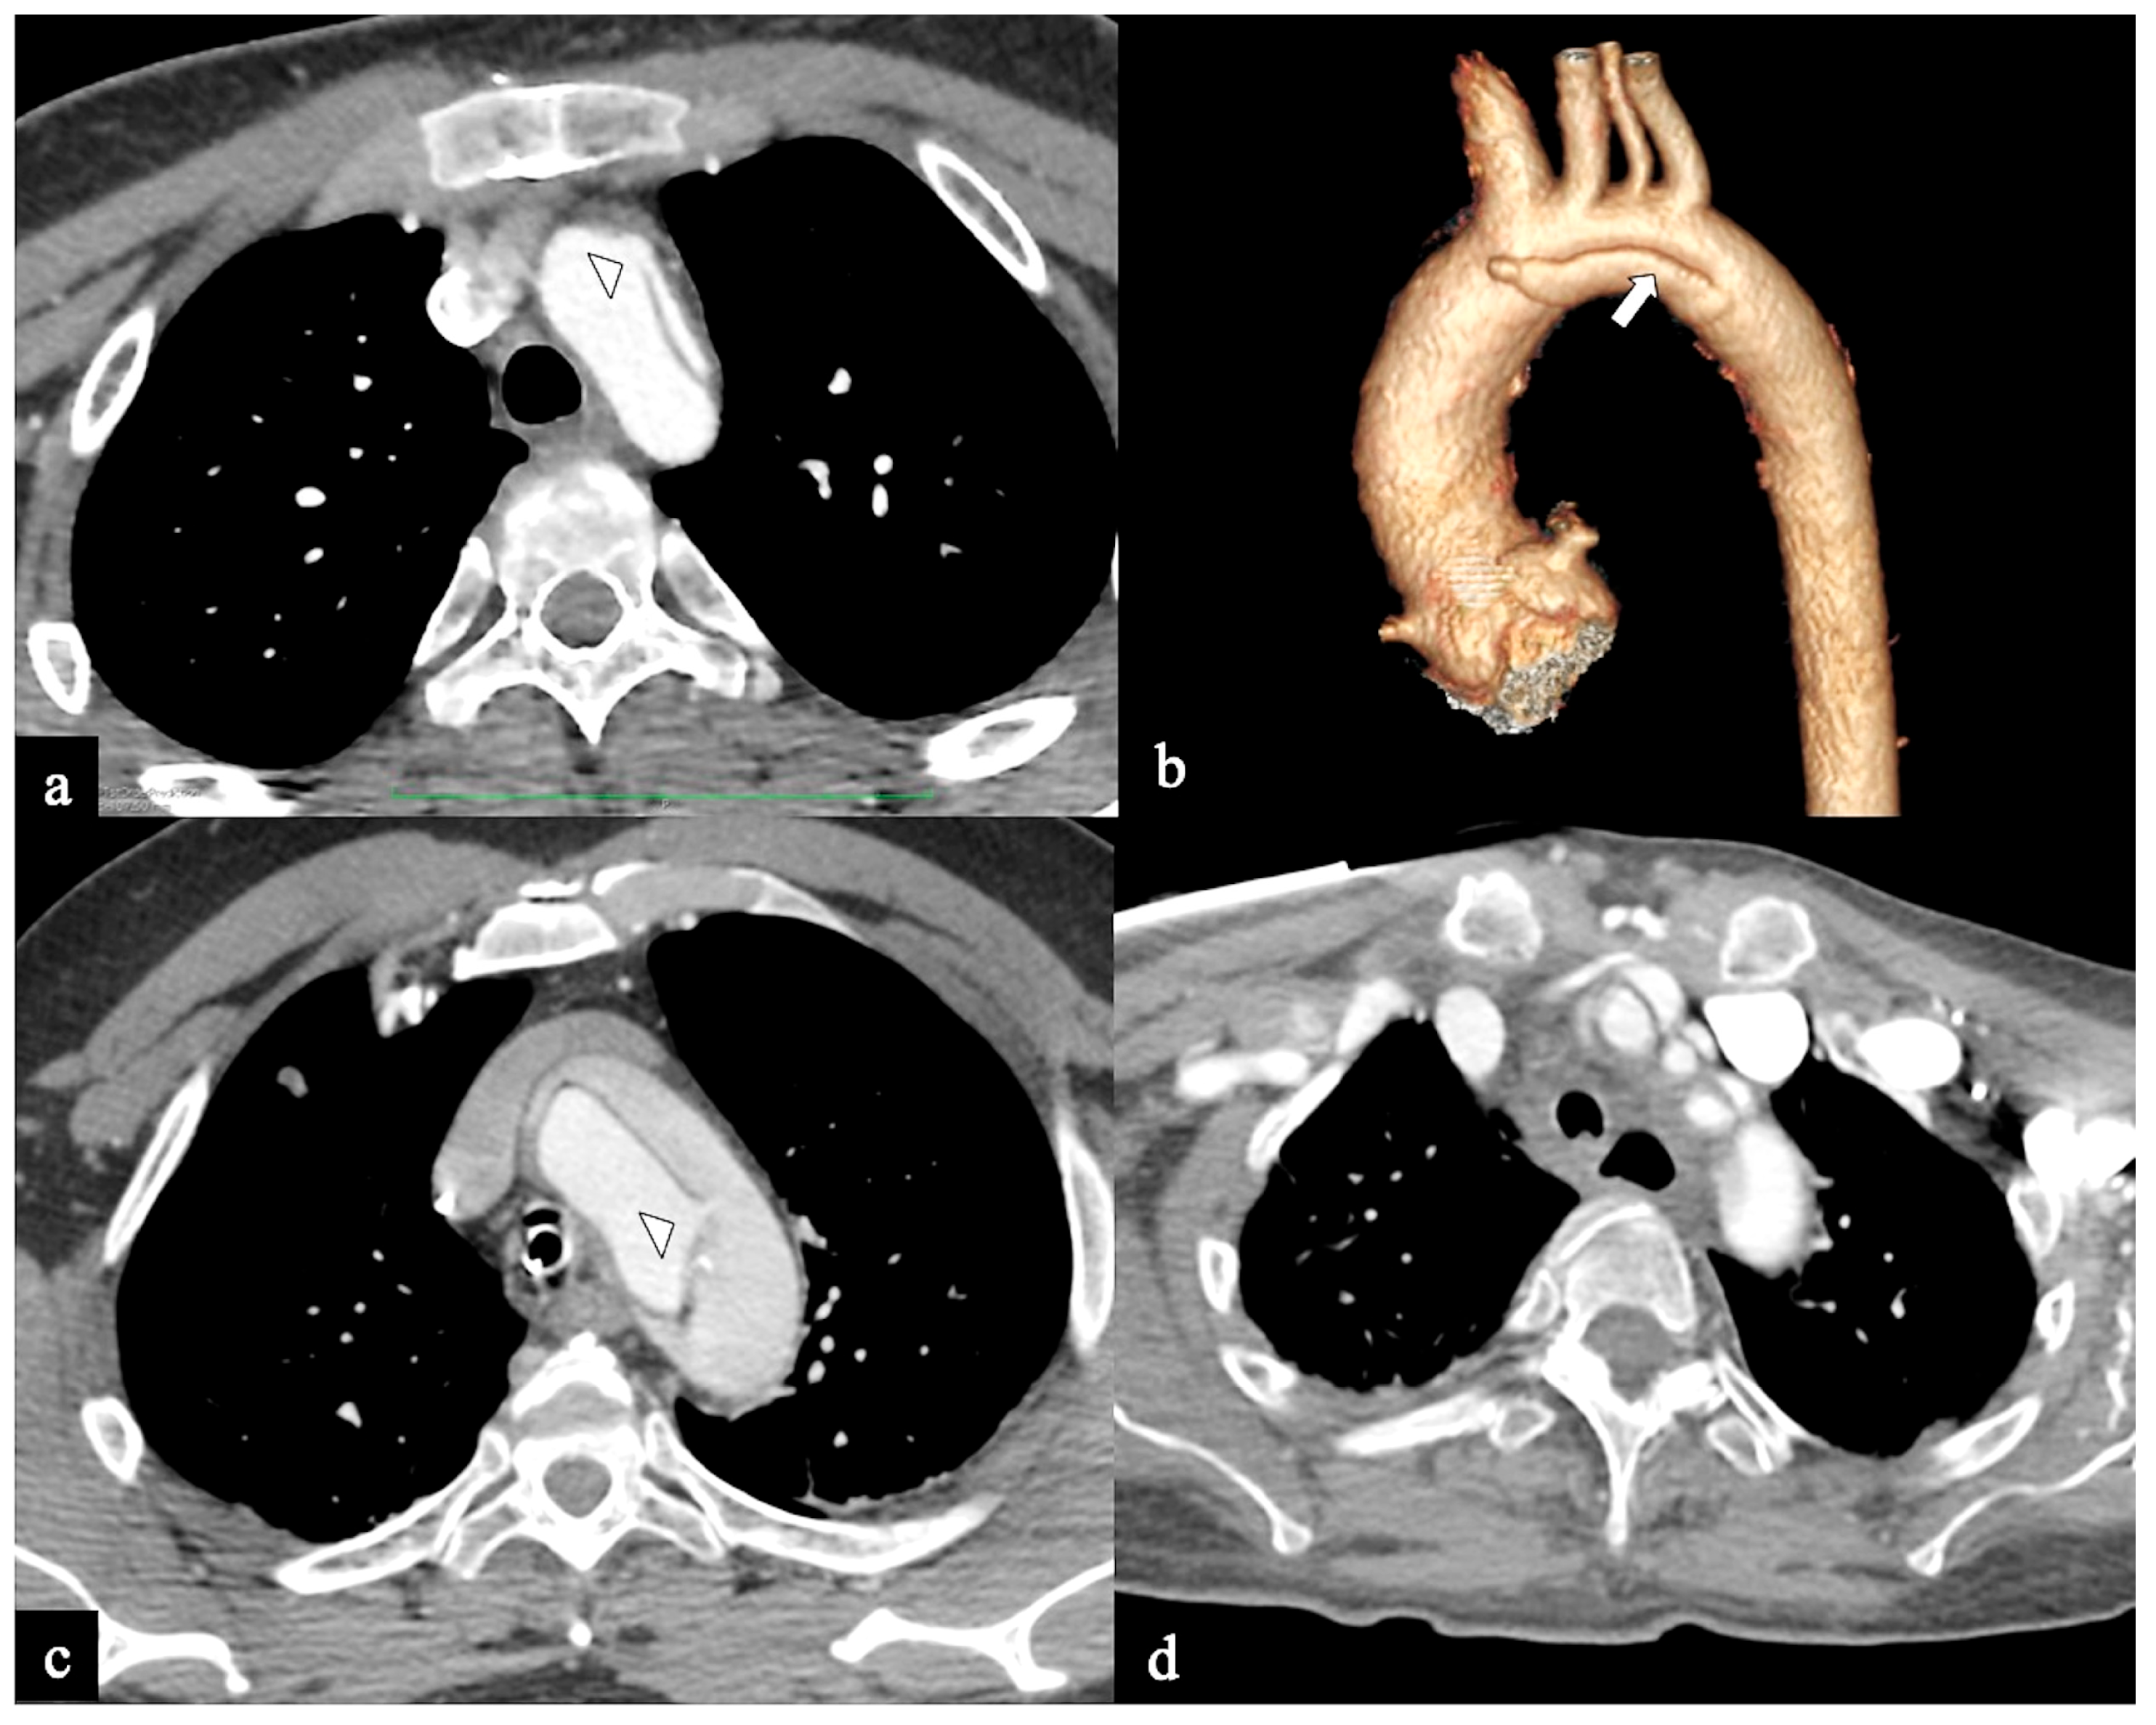

- In Configuration 2, the primary ET is situated within the aortic arch, and the dissection flap is confined solely to the arch (Arch alone). the primary ET is located in the aortic arch and the dissection flap is limited to the arch (Arch alone). This very uncommon configuration occurred in 4 (11%) patients (Figure 4) and is a very rare clinical entity. Configuration 2 is similar to the “group B” definition provided half of a century earlier by Dubost and colleagues [36], reported by Pasic in 1999 [37], and again proposed by Urbanski in 2016 [26]. An amount of 2/4 of these Arch alone patients received continued medical management with close imaging surveillance, and one- and two-year follow-up CTA examinations showed no dissection progression; 2/4 patients underwent hybrid or open surgical repair, one due to persisting pain, and the other one for cerebral malperfusion on follow-up CT.